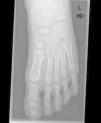

En las radiografías solicitadas (figs. 1–3) no se evidencian líneas de fractura, objetivándose un escafoides aumentado de densidad, con morfología en disco, esclerosis y fragmentación siguiendo un eje lineal. Estos hallazgos son sugerentes de necrosis aséptica del escafoides o enfermedad de Köhler.

Radiografía oblicua del pie izquierdo en la que se aprecian los mismos hallazgos descritos en la figura 1.

Detalle de la figura 1 en la que se aprecia el hueso escafoides aumentado de densidad con morfología en disco, esclerosis y fragmentación siguiendo un eje lineal. Hallazgos indicativos de necrosis aséptica.